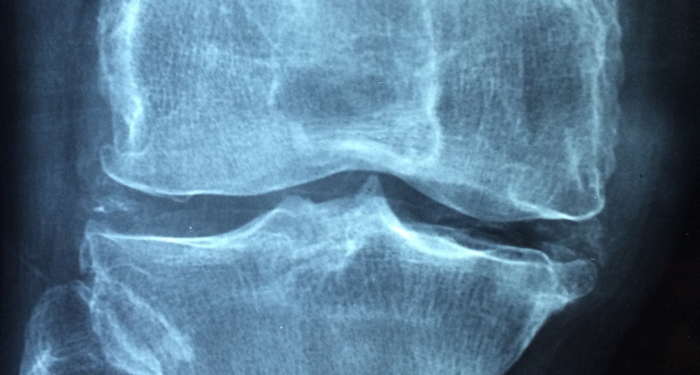

Rheumatoid arthritis (RA) adalah penyakit autoimun degeneratif, yaitu saat sistem kekebalan tubuh sendiri menyerang lapisan sendi sehingga mengalami peradangan. Dalam waktu lama, peradangan akan mengganggu jaringan sehingga pengidapnya bisa merasa sakit bila menggerakkan anggota tubuh yang terpengaruh.